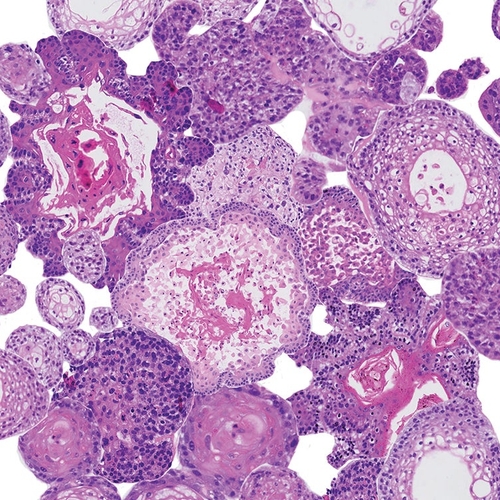

Onder hoofd-halskanker verstaan we alle kwaadaardige tumoren van de bovenste lucht- en voedselwegen. De belangrijkste locaties zijn de mondholte, de keelholte, het strottenhoofd, de speekselklieren en de neus- en neusbijholten.

Er zijn verschillende soorten hoofd-halskanker, maar ze hebben veel overeenkomsten. Bijvoorbeeld in de manier waarop zij ontstaan en de manier waarop zij uitzaaien. Ook zijn er overeenkomsten in hoe we de ziekte opsporen (de methoden van diagnostisch onderzoek), behandeling en revalidatie.